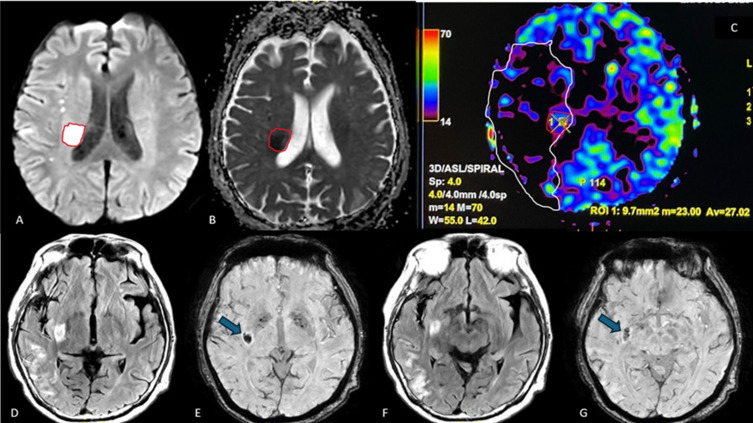

Ischemic stroke is the second leading cause of mortality and morbidity worldwide. Due to the urgency of implementing immediate therapy, acute stroke necessitates prompt diagnosis. The current gold standards for vascular imaging in stroke include computed tomography angiography (CTA), digital subtraction angiography (DSA) and magnetic resonance angiography (MRA). However, the contrast agents used in these methods can be costly and pose risks for patients with renal impairment or allergies. The aim of this paper is to provide a comprehensive overview of current MRI techniques and sequences for evaluating ischemic stroke, emphasizing the importance of non-contrast options and their clinical implications for radiologists in the diagnosis and management of ischemic stroke. Standard MRI sequences-such as T1-weighted imaging (T1WI), T2-weighted imaging (T2WI), fluid-attenuated inversion recovery (FLAIR), diffusion-weighted imaging (DWI), DWI-FLAIR mismatch, and apparent diffusion coefficient (ADC)-are essential for determining infarct location, volume, and age. Additionally, incorporating susceptibility-weighted imaging (SWI) sequence aids in identifying signs of hemorrhagic transformation within the infarcted region. Advanced techniques like arterial spin labeling (ASL) can serve as a non-contrast alternative for mapping cerebral blood flow (CBF) and allowing for comparison between infarcted and healthy brain areas. Adding ASL to the routine sequence allows ASL-DWI mismatch analysis that is useful for quantifying salvageable tissue volume and facilitate timely recanalization, while time-of-flight (TOF) MRA and magnetic resonance venography (MRV) help assess venous thrombosis, stenosis, or arterial occlusions. Finally, MR spectroscopy can provide insights into critical brain metabolites, including N-acetylaspartate (NAA), and lactate (Lac) to determine patient prognosis. Current MRI technology provides a myriad of sequence options for the comprehensive evaluation of ischemic stroke without the need for contrast material. A thorough understanding of the advantages and limitations of each sequence is crucial for its optimal implementation in diagnosis and treatment.